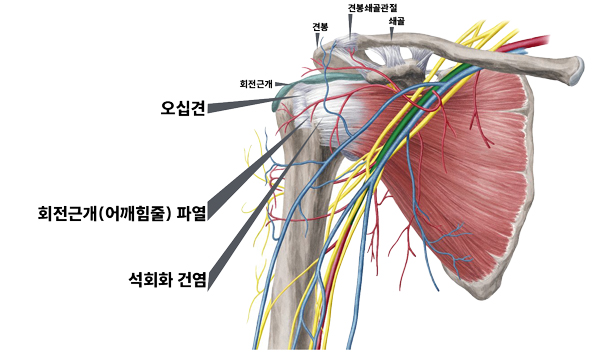

회전근개파열

어깨를 감싸고 있는 힘줄(극상건,극하건,견갑하건,소원건)을 회전근개라 말하며 나이가 들면서 근육이 약해지고 일상생활 중 무리하거나 다쳐서 손상되거나 끊어지는 현상을 말합니다. 어깨통증의 원인 중 90%를 차지하며 파열되면 자연치유되는 경우는 거의 없어서 봉합수술이 필요합니다.

석회성건염(Calcific tendinitis)

어깨의 힘줄로 가는 혈액공급이 줄어들어 힘줄세포가 연골세포로 변해 석회가 발생되는 질환을 말합니다

어깨충돌증후군

젊은 나이나 어깨 관절이 건강할 때는 견봉과 어깨 근육 사이의 여유가 충분하지만 나이가 들어 근력이 약해지거나 반복적으로 어깨를 사용했을 때, 외상으로 다쳤을 경우에 견봉과 어깨 근육 사이에 마찰이 일어나 통증을 발생시키는 현상을 말합니다.